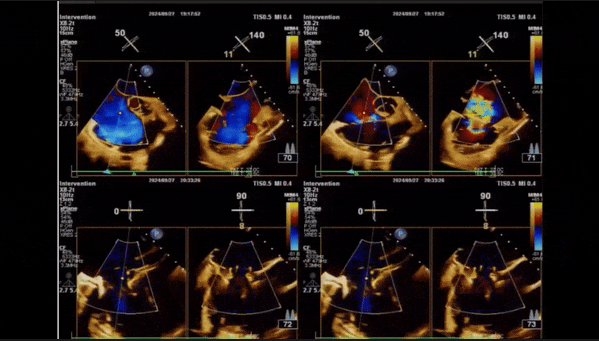

術后即刻返流

術后即刻返流三維

術中經食道超聲輔助下可見LuX-Valve Plus夾持件抓捕瓣葉狀態良好,夾持件在位,室間隔錨定位置良好,假體瓣膜整體錨定狀態穩固。

術后即刻經食道超聲可見,三尖瓣假體瓣膜位置合適,牛心包瓣葉運動狀態良好,開閉正常,瓣周及瓣葉對合緣處未見明顯返流,心電圖及心包狀態較術前無明顯變化。

術前術后返流情況對比